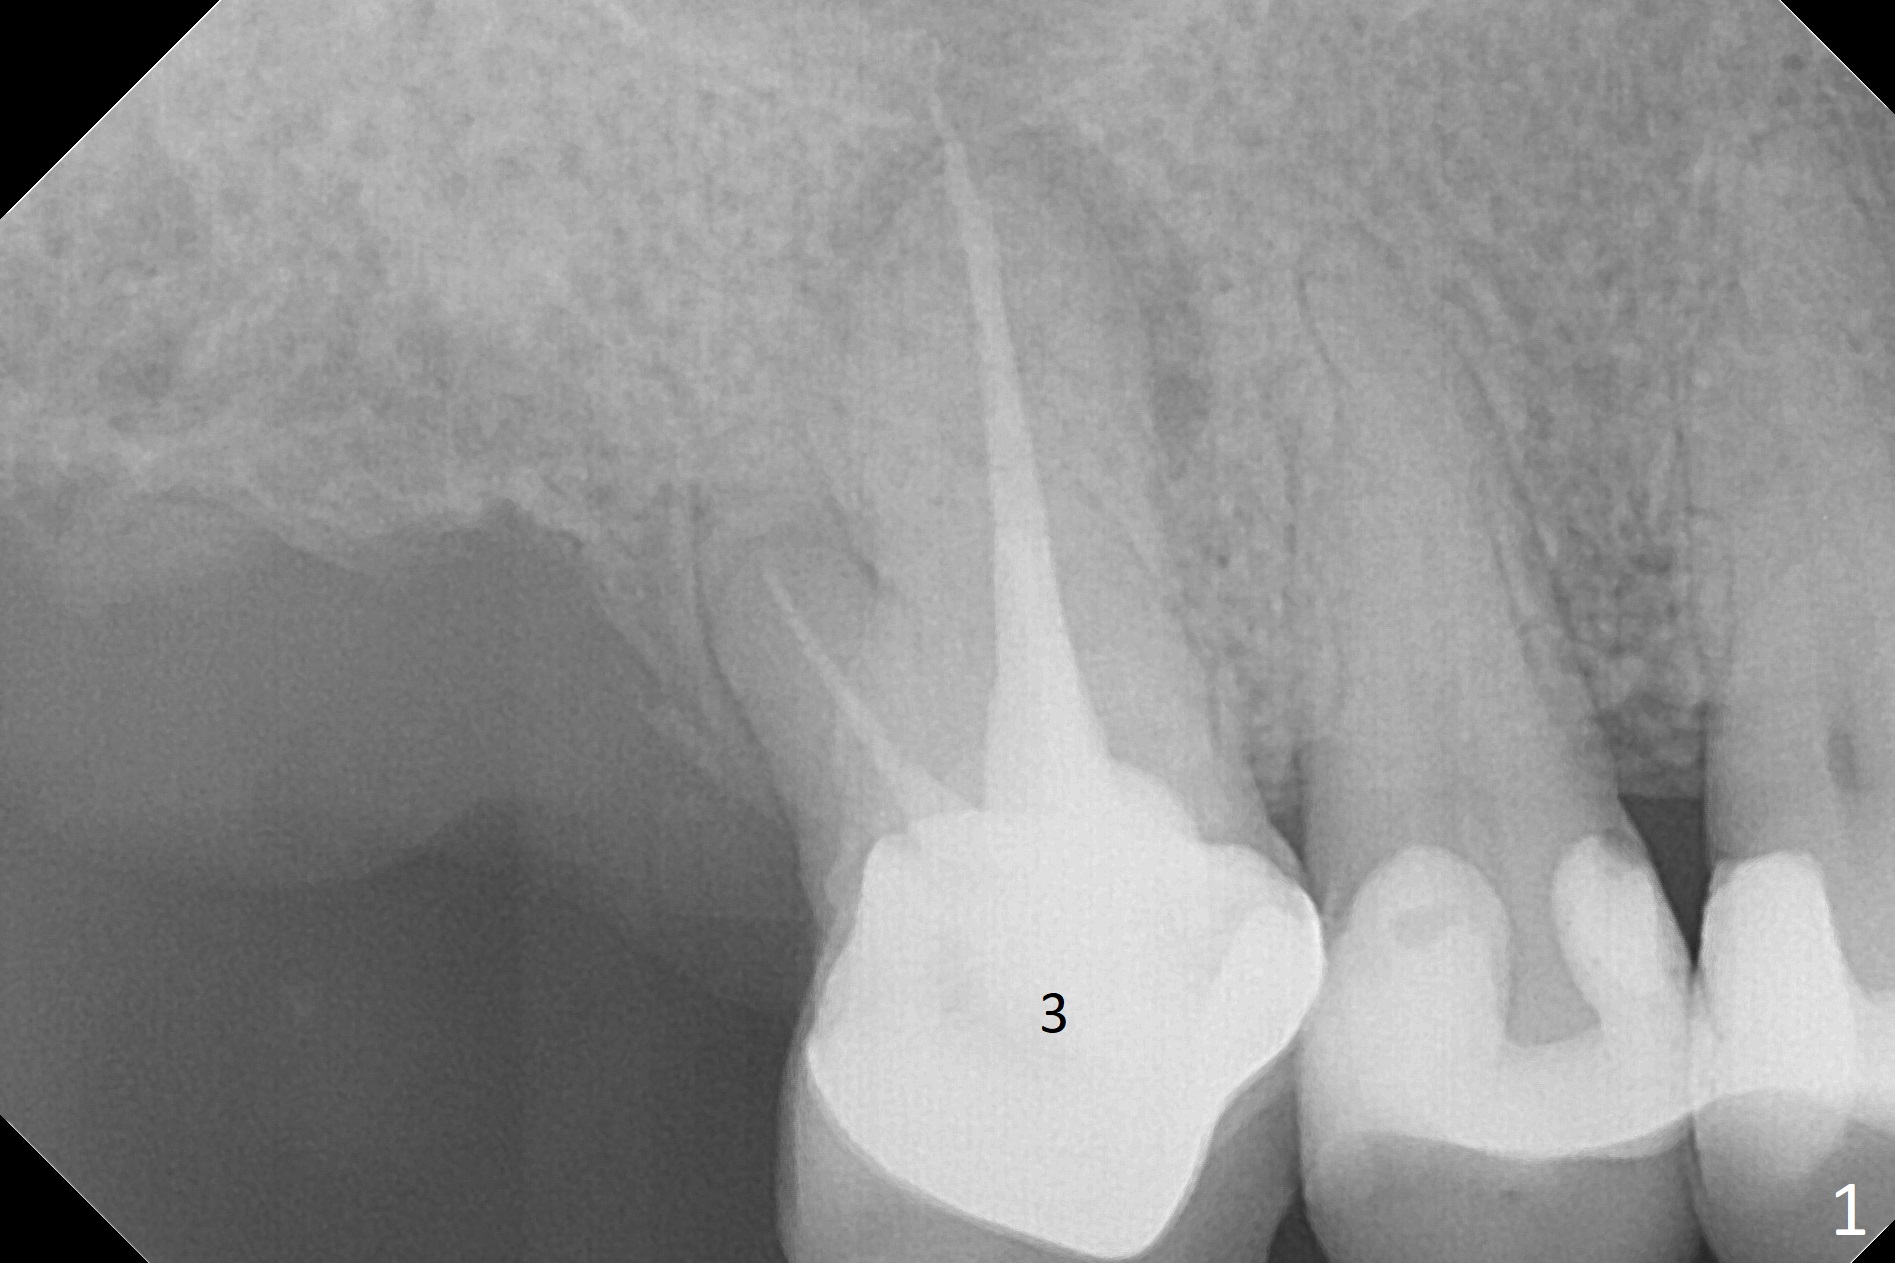

A 53-year-old woman wants to extract the tooth #3 with recurrent apical periodontitis (Fig.1). Socket preservation is conducted (Fig.2). The tooth is terminal in the arch and difficult to keep periodontal or acrylic dressing in place. To overcome the situation, a prefabricated space maintenance is placed without cementation because of its inherent fitness (Fig.3). Periodontal dressing (Fig.4 D) appears to be retained in place. The spacer is lost prematurely due to no cement, but the wound appears to be healing 13 days postop (Fig.5,6). The socket heals 3 months postop (Fig.7,8). However the ridge is narrow 19 months postop (Fig.9, as compared to that of the tooth #14 (Fig.10)).